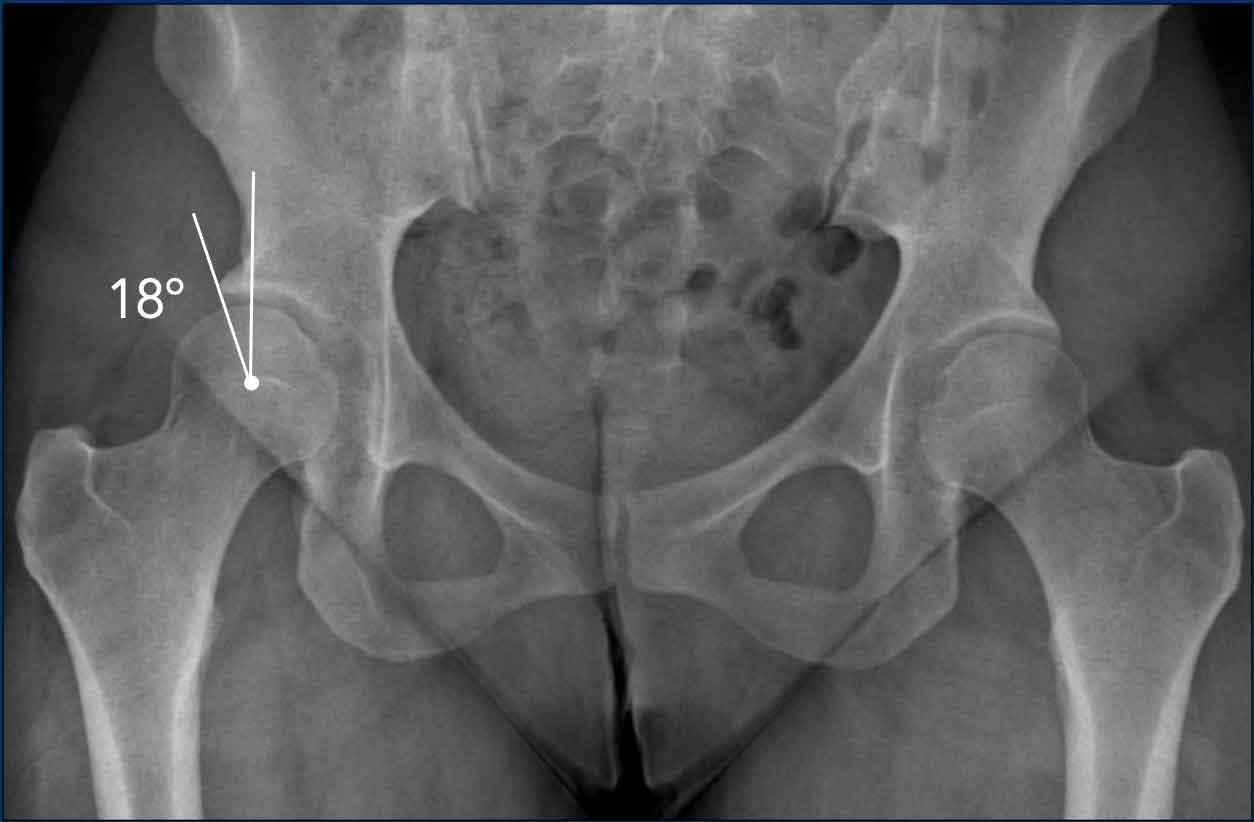

Loạn sản ổ cối

Loạn sản ổ cối hông không được nhận biết đôi khi bị nhầm lẫn về mặt lâm sàng với các triệu chứng liên quan đến FAI.

Điều quan trọng là cũng cần báo cáo bất kỳ tình trạng thiếu che phủ hoặc loạn sản tiềm ẩn nào (tức là L-CEA < 20 độ).

Nhiều chuyên gia cho rằng L-CEA từ 20 đến 25 độ là loạn sản giới hạn.

Hình ảnh này của một nam giới 23 tuổi có biểu hiện các triệu chứng liên quan đến hông.